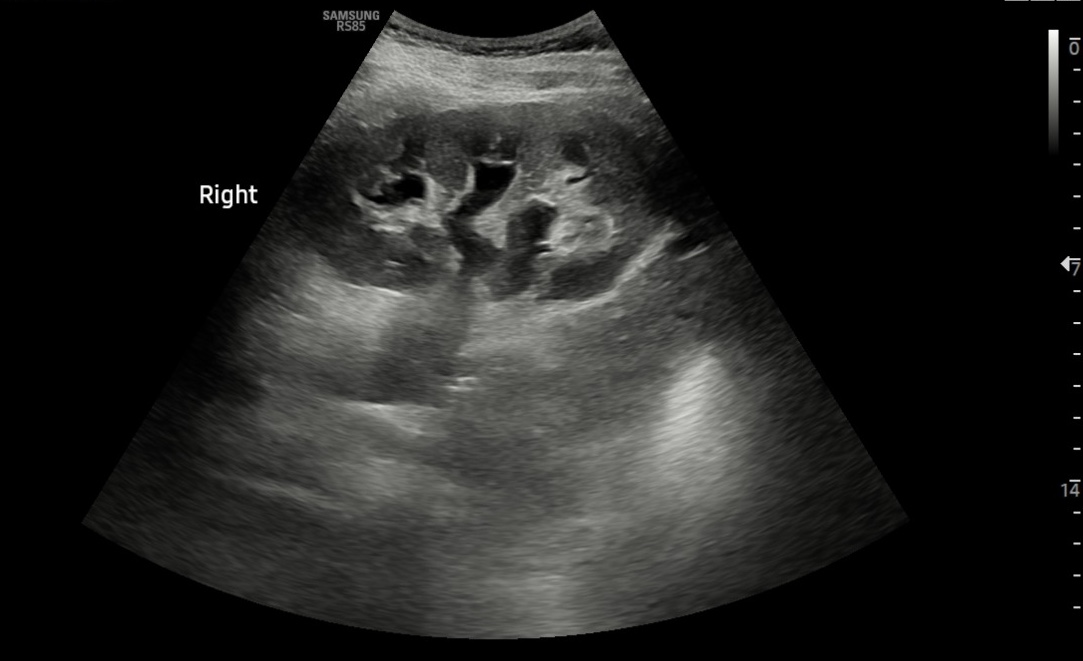

Hallazgos ecográficos

• Ambos riñones de tamaño y parénquima conservados. Objetivamos una hidronefrosis derecha grado 2. Parece apreciarse una imagen compatible con litiasis en uréter proximal y mínima cuña de líquido libre en polo inferior del riñón derecho.